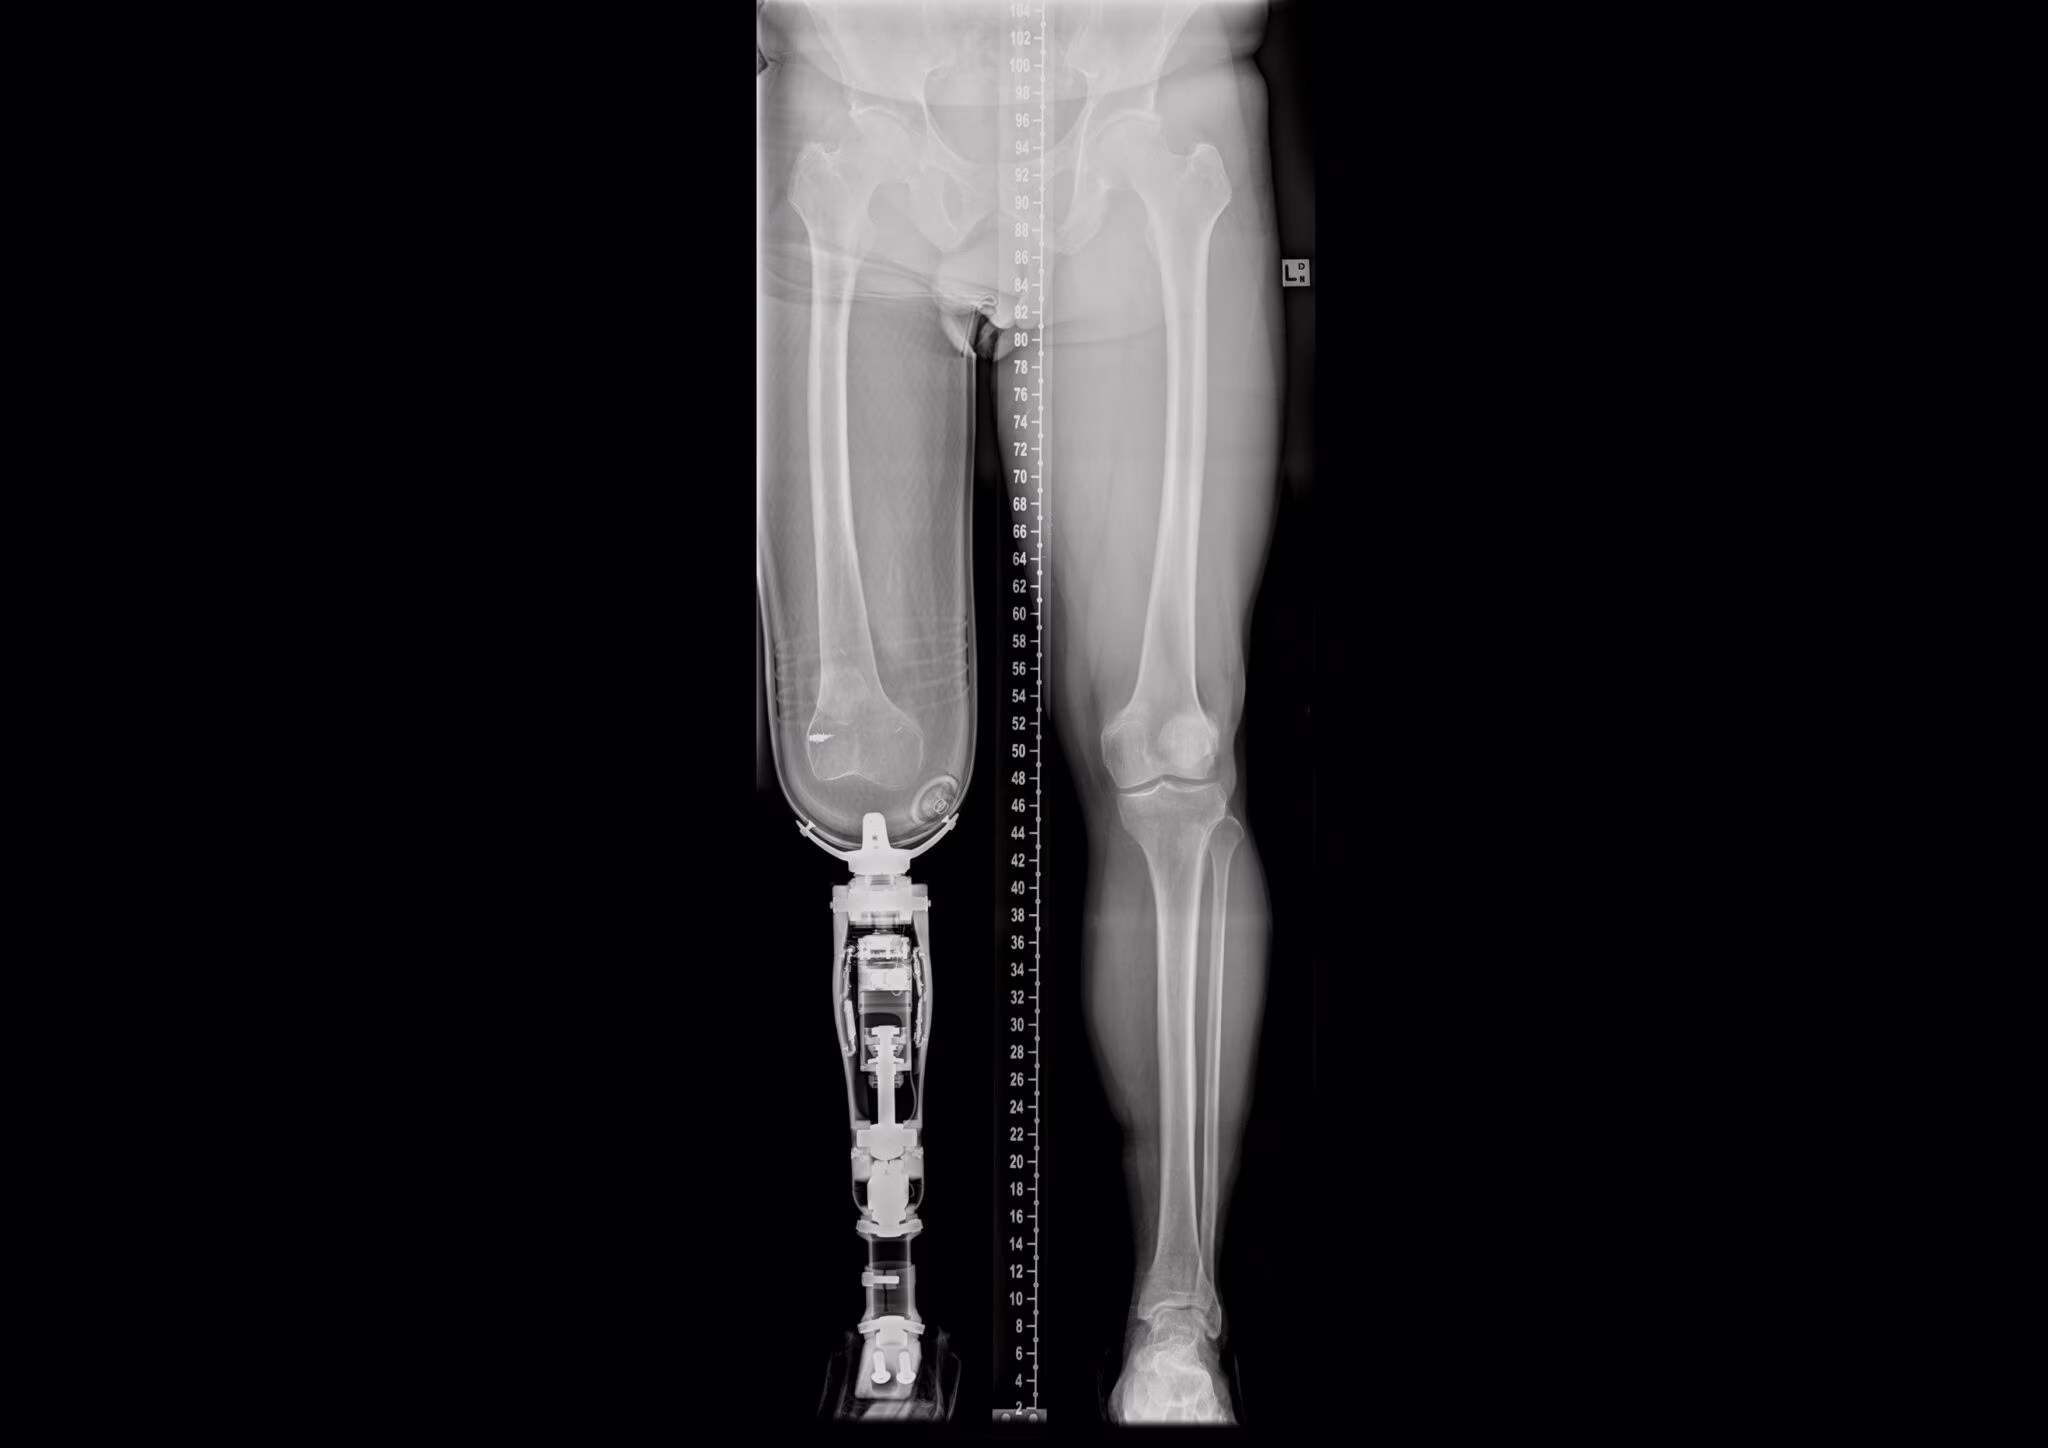

Il processo di riabilitazione inizia circa 2-3 mesi dopo la seconda operazione ed è piuttosto lungo e articolato. Durante le prime settimane il paziente deve utilizzare una protesi detta “da allenamento”, molto più corta rispetto a quella definitiva. L’arto viene gradualmente caricato tenendo monitorata la soglia del dolore e sottoponendo il paziente ad analisi periodiche con raggi-X per verificare lo stato del processo di osteointegrazione. L’iter riabilitativo segue il protocollo ideato da Branemark che permette di scegliere tra due tipologie di riabilitazione a seconda delle esigenze del paziente.